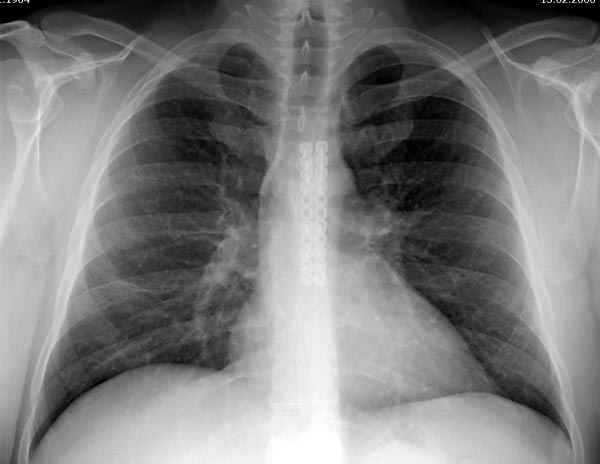

Пару лет назад коллега из грудной хирургии направил больного с хроническими жалобами на боли по поводу ложного сустава грудины.

Оперировали вместе с грудным хирургом и в нашем случае главной причиной была болезненность. Во время операции приняли все меры предосторожности недопущения прокола средостения (см. на 4 снимке близкий контур сердца!!)

Ложный сустав зафиксирован двумя пластинами 2.4 мм (locking plate) позаимствованными из челюстно-лицевой хирургии, с костной пластикой, все остальные пластины мне показались слишком толстыми, грубые для грудины или отсутсвовали возможности создания угловой стабильности.

Рентген снимки во время операции и последние сделаны на днях.